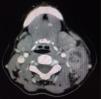

La analítica inicial reveló leucocitosis 12,2×109/l, neutrofilia 9,64×109L, VSG 49mm/h, PCR 3,39mg/dl. Las serologías de (VIH, VHB, VHC, VEB, CMV, sífilis) fueron negativas. En la TAC de cuello y tórax aparecía una masa multinodular en el cuello izquierdo nivel IIA-IIB y III con necrosis central de 4×2,8cm (fig. 2). La radiografía de tórax era normal. Se sospechó etiología infecciosa o enfermedad linfoproliferativa. Se practicó PAAF que fue no concluyente por escasa muestra.